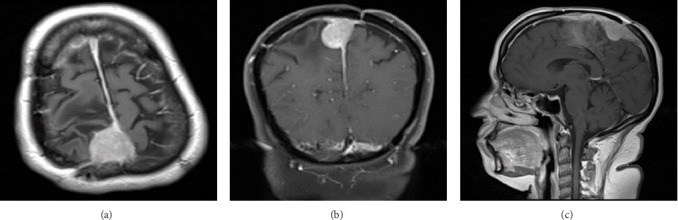

Background and importance: Meningiomas are one of the most frequent primary central nervous system (CNS) tumors. According to the World Health Organization (WHO) classification of brain tumors, meningiomas are categorized into Grade 1 (benign meningioma; 80%), Grade 2 (atypical meningioma; 4%-15%), and Grade 3 (anaplastic meningiomas; 1%-3%). Grade 2 meningioma has a higher recurrence rate, ranging from 29%-52%. However, the transformation from atypical meningioma into benign meningioma is poorly understood. The present article describes a patient with Grade 2 meningioma that transformed into a benign subtype. Case presentation: A 51-year-old female with a history of seizures, presented with left-sided progressive weakness. Radiological imaging revealed a large extra-axial parasagittal lesion measuring 5 cm × 5 cm × 4.8 cm, suggestive of meningioma. The patient underwent subtotal resection of the lesion. Histologically, the tumor was in favor of Grade 2 meningioma. Radiological follow-up 8 years postoperatively revealed a recurrent meningioma. The patient underwent right-sided craniotomy and resection of the parasagittal meningioma. The histopathological features were suggestive of a Grade 1 meningioma. Conclusion: The transformation from atypical to benign meningiomas is rarely reported and the mechanism remains unclear. The present case provides insights into the natural history of this entity, describes possible etiologies, and lists the surgical management with an emphasis on preoperative radiological imaging and histopathological investigations.